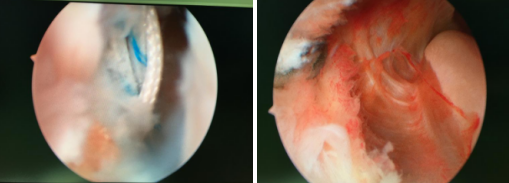

利用踝关节镜+骨科机器人,sararz足踝科完成踝关节韧带断裂合并骨折修复手术

33岁的肖先生,崴脚导致肿痛、淤青,难以下地,来到必威官方首页官网betway足踝科治疗。检查结果患者左距骨骨折,三角韧带、距腓前韧带、跟腓韧带损伤,需要做韧带修复和骨折复位手术。

讨论后,石荣剑副院长徐明亮主任手术团队为患者进行了关节镜下韧带修复术和机器人辅助下骨折固定术。首先利用踝关节镜探查距腓前韧带断裂,用可吸收带线锚钉修复;镜下探查复位保证距骨关节面平整;机器人定位,闭合平行打入两枚空心螺钉,骨折固定精准稳定。

该手术也是我省首次利用踝关节镜和骨科机器人完成的足踝关节韧带撕裂合并骨折修复手术,该微创手术既缩短了手术时间和术后恢复期,也降低了并发症发生率,效果很好,患者满意度更高。

韧带受伤

右外踝骨折(左),术中(右)